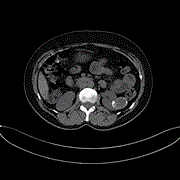

Primary hydatid cyst looked like renal cell carcinoma: case report

Irzi Mohamed and others

Journal of Surgical Case Reports, Volume 2020, Issue 9, September 2020, rjaa231, https://doi.org/10.1093/jscr/rjaa231